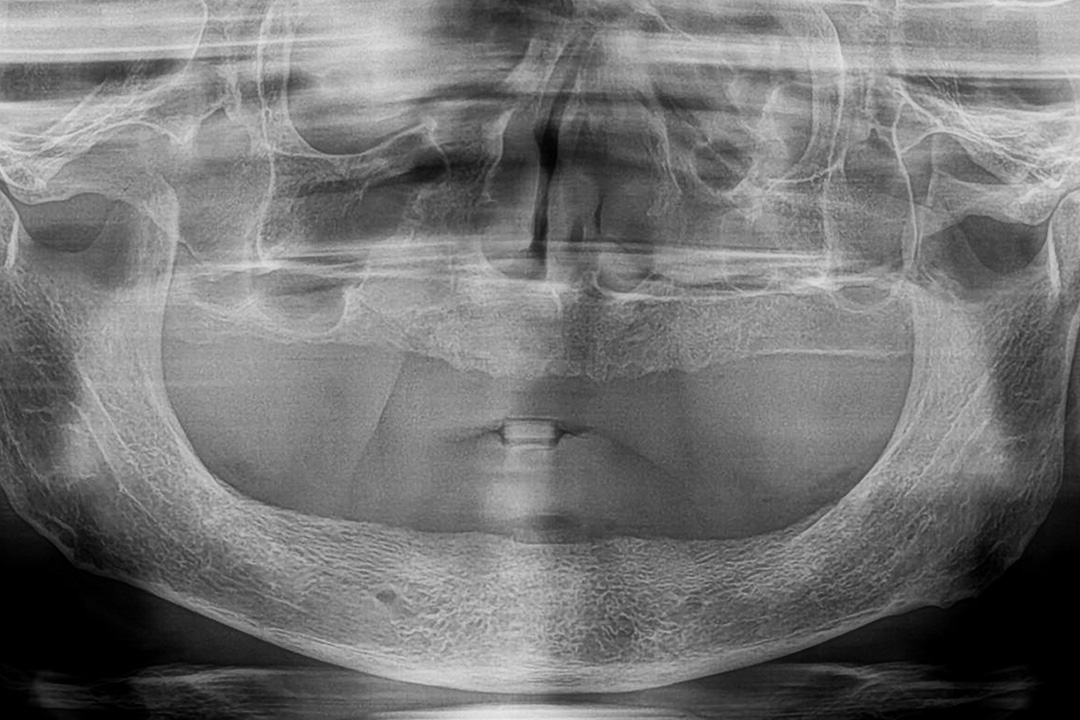

Zygomatic implants work by anchoring into the zygoma, or cheekbone, rather than the maxillary bone of the upper jaw. The procedure begins with a thorough evaluation, including imaging studies like CT scans, to assess the bone structure and plan the implant placement. The implants themselves are longer than traditional dental implants, designed to reach the dense zygomatic bone.

Initially, a comprehensive pre-surgical evaluation, including imaging studies like CT scans, is performed to map out the anatomy and plan the implant placement.